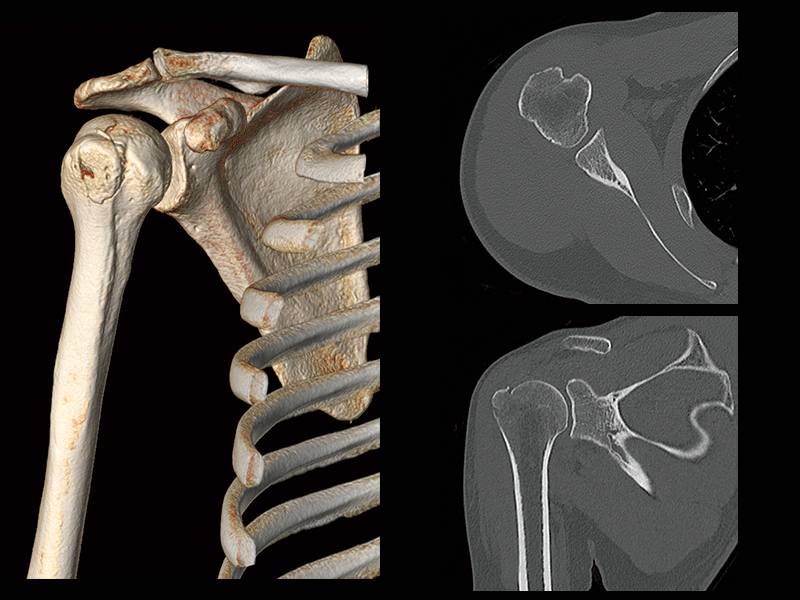

Humeral greater tuberosity fracture